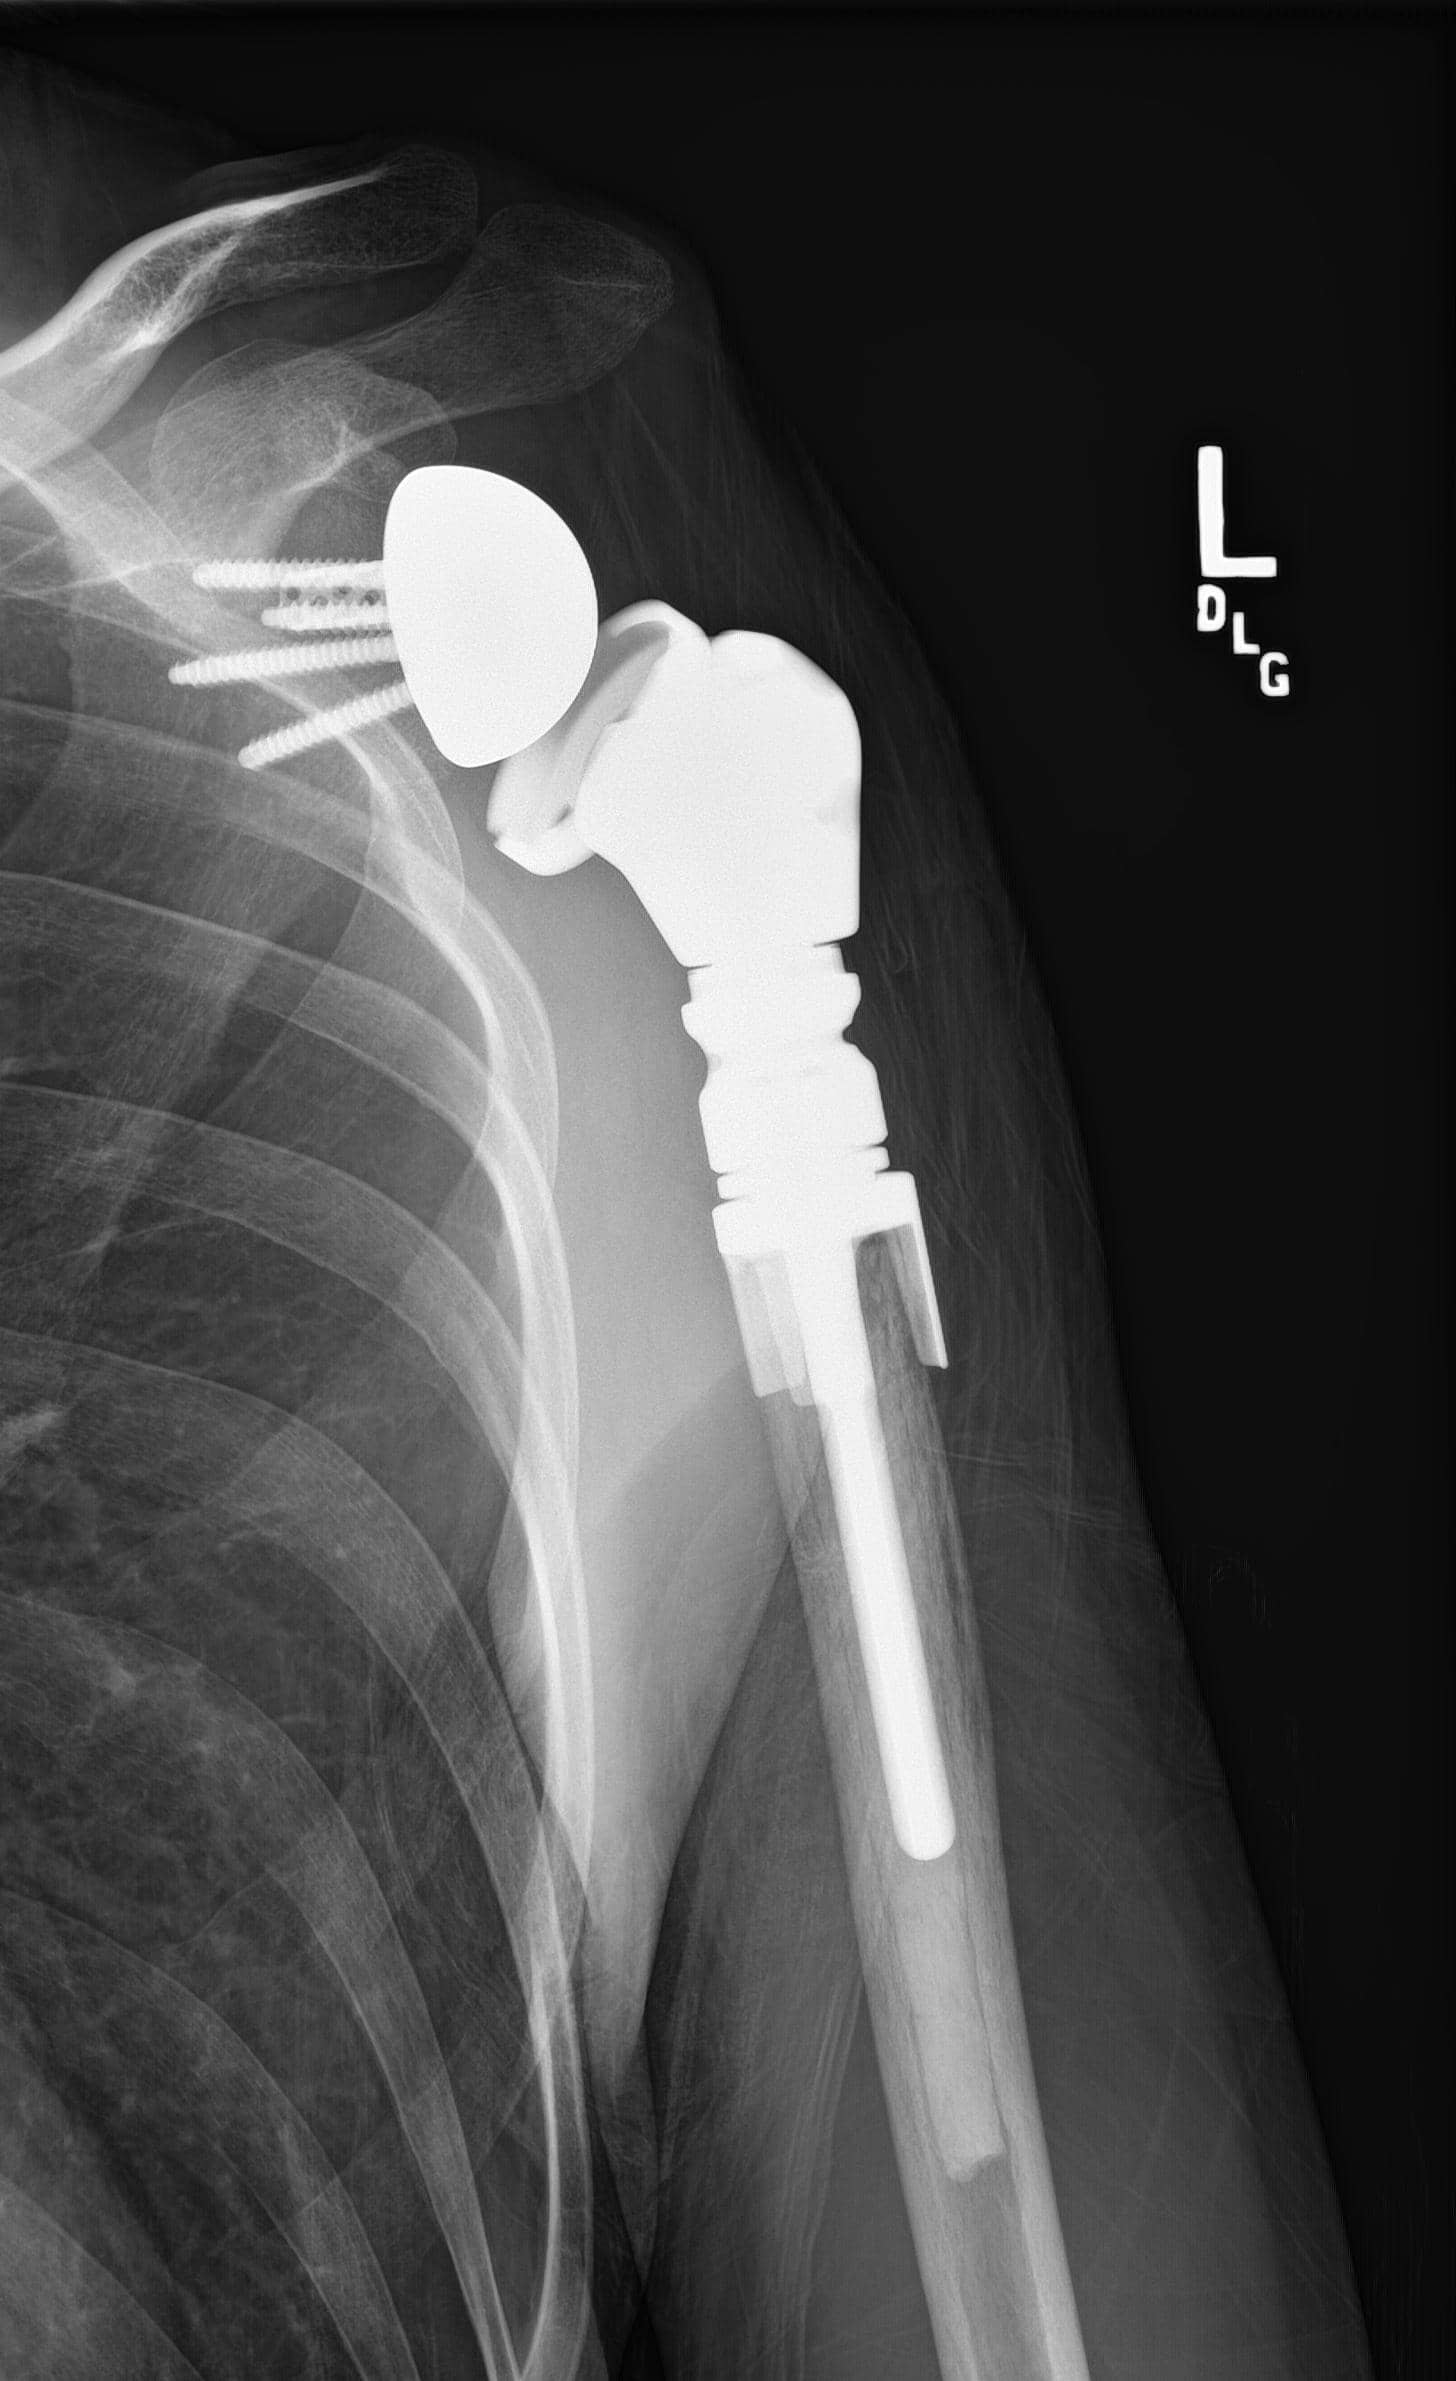

Upper Humerus

MBD of the upper humerus near the shoulder may be treated with a variety of techniques, depending upon how extensive the cancer is. Sometimes, a portion of the upper arm and shoulder needs to be replaced with an artificial metal prosthesis (upper humeral prosthetic replacement). Generally,  only the arm side of the shoulder joint is replaced when a patient has metastatic disease. The socket side of the joint is usually not involved.

These surgeries are generally more complex than the shoulder replacements used for shoulder arthritis, and MBD patients often have less function due to rotator cuff removal and reattachment to the metal prosthesis.

upper humeral prosthetic replacement

Large metastatic tumors in the upper arm near the shoulder often require some type of artificial replacement. This X-ray shows an artificial replacement of the upper arm bone.